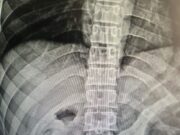

18:00 – Reeducando é hospitalizado com dor no estômago e raio-x mostra minicelular no...

Reeducando é hospitalizado com dor no estômago e raio-x mostra minicelular no órgão